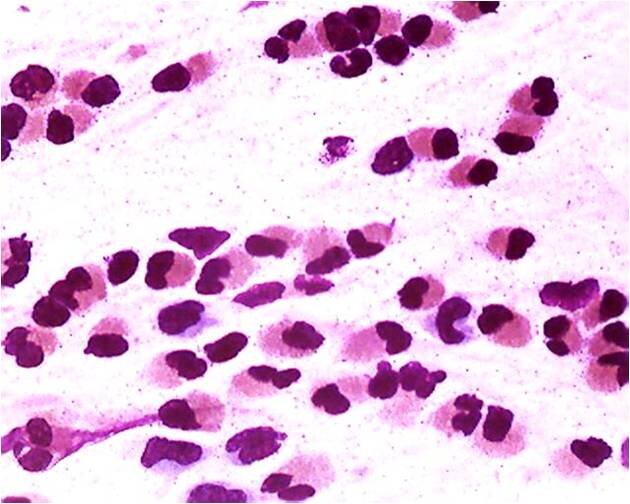

Часто назначаемое исследование - назоцитограмма, когда исследуется отделяемое из носа - позволяет выявить изменения, характерные для аллергических реакций организма или для инфекции.

Назоцитограмма. Аллергический ринит. Большое количество эозинофилов. Окраска по Папенгейму. х1000

За период 2019-2021 гг. обследовано 1447 человек с клиническими признаками ринита, возраст обследованных от 2 до 15 лет. Средний уровень эозинофилии за год составил 37%.